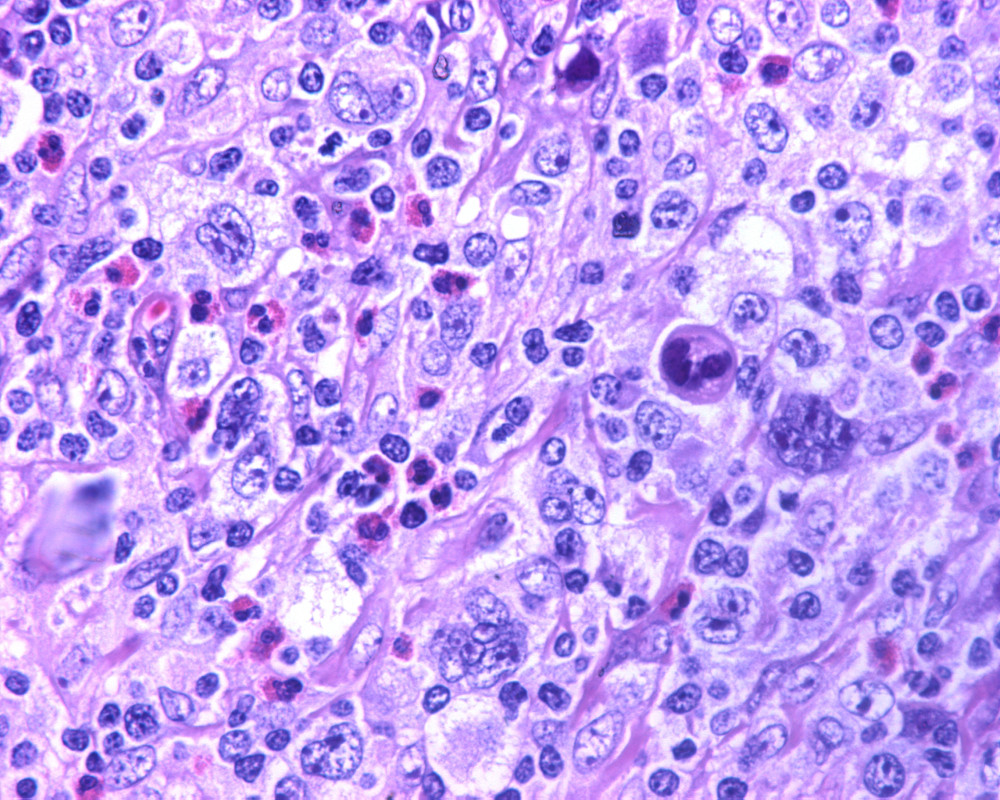

Biopsia de ganglio linfático.

-¿Cuál es su diagnóstico de trabajo por morfología y su diferencial?

DIAGNÓSTICO: LINFOMA DE HODGKIN CLASICO, ESCLEROSIS NODULAR, VARIANTE SINCICIAL